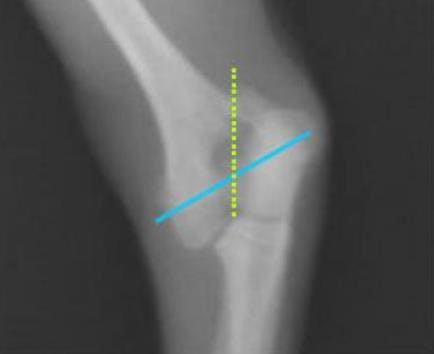

무릎뼈 확인

먼저 발이 닿지 않는 의자에 앉은 후 무릎뼈를 꾸욱 눌러보시길 바랍니다. 이때 무릎뼈와 다리 사이에 있는 연골의 있어 헷갈릴 수 있는 만큼 예민하게 살펴보시길 바랍니다.

만약 성장판이 닫힌 어른의 경우라면 말랑거리고 안으로 들어가지만 그렇지 않은 아이의 경우 조금 다른데요. 약간의 딱딱함이 느껴진다면 성장판이 아직까지 열려 있다고 생각하실 수 있습니다.